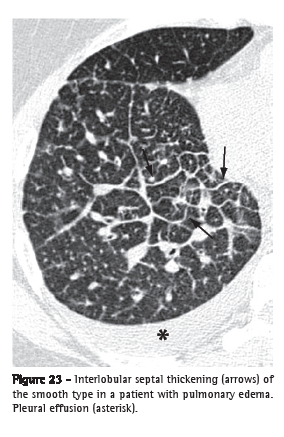

Interlobular septal thickening (espessamento de septos interlobulares)

Interlobular septal thickening is the thickening of the connective tissue septa separating the secondary pulmonary lobules. It is radiographically characterized by thin linear opacities, also designated Kerley B lines. It is usually in close contact with the lateral pleural surface, near the costophrenic sulci, at a right angle to the pleural wall. Currently, the terms "septal lines" or "septal thickening" have gained favor over Kerley lines. On HRCT scans (Figure 23), the thickening of the interlobular septa is characterized by the presence of linear opacities that delimit the secondary pulmonary lobules, more easily characterized in the subpleural region, in which it has the aspect of lines at right angles to the pleural surface.(3,44) In the central regions of the lungs, the thickening of the septa of adjacent lobules results in the aspect of polygonal arches. Septal thickening can be secondary to changes in any of its components (veins, lymphatic vessels or connective tissue) and is a finding common to various lung alterations; however, its presence is particularly highlighted in cases of pulmonary edema and lymphangitic carcinomatosis. Septal thickening can be smooth (Figure 23), nodular (Figure 24) or irregular. This differentiation can aid in the differential diagnosis.

Secondary pulmonary lobule (lóbulo pulmonar secundário)

The secondary pulmonary lobule is the smallest anatomic unit of lung delimited by a septum of connective tissue. It is polyhedral in shape, measures 1.0-2.5 cm in diameter and contains a variable number of acini.(45) The center of the lobule is formed by the bronchiole and its accompanying pulmonary artery, lymphatic vessels and adjacent interstitium. In its periphery, the connective tissue forms thin septa designated interlobular septa, which contain small pulmonary veins and lymphatic vessels (Figure 25). In normal patients, the interlobular septa are better identified in the anterior, lateral and paramediastinal peripheral regions of the upper and middle lobes, as well as in the peripheral region of the anterior diaphragmatic region of the lower lobes, tending to be incomplete or absent in the remaining lung regions. The interlobular septa are easily recognized on HRCT scans when the septal interstitium is affected (Figures 23 and 24).(3)